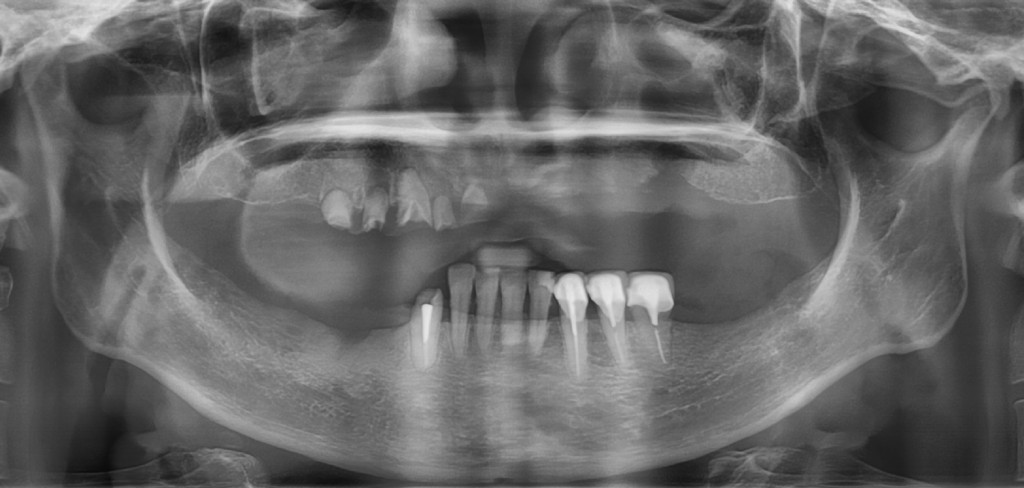

殘根拔除後,植入6支人工牙根